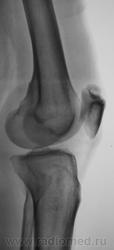

Травма. Направлен на рентгенографию коленного сустава

Несросшийся апофиз надколенника, деструкции не вижу

Без костных травматических изменений.

Такое развитие надколенника. Хотя может быть и травматический разрыв фиброзных сращений.

Подумала и решила исправить запись -исход остеохондропатии надколенника

А, может быть просто пателла бипарцита?

Можно уточнение ? Край основной массы надколенника неровный, углы заострены и щель выглядит неравномерной -это обычная картина при удвоении надколенника ?

И мне это не понравилось. И по боковой - впечатление о смещении фрагмента.

Мужчина 39 лет, жалоб нет. Обратил внимание на разницу с другим коленным суставом (выпирает). Второй сустав на снимке без изменений. Травм утверждает, что не было.

Получается просто удвоение наколенника ....не попадалось